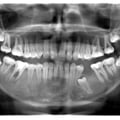

Імплантація 16,17,18 без врахування жодних правил оклюзії та знань в імплантології

Руйнування зубів - результат тривалого користування бюгельними знімними протезами

Лікування карієсу дистопованого 48 зуба не є вирішенням даної патології. Дистопія зуба мудрості провокує виникнення карієсу 47 зуба. Даний зуб має бути видалений

Пацієнтка А. (10 років). Первинна адентія внаслідок вродженої ектодермальної дисплазії

Відсутність адекватного лікування, як наслідок - 14,15 зуби приймають участь в акті дихання

Патологія прорізування зубів. Екструзія дистопії 23,24 ортодонтичним способом

Залізна людина )))

Неправильне зубне протезування - заклали зуби )))

Максимальна атрофія щелеп - результат тривалого користування знімними протезами

Міграція 28 зуба під очницю

Не кваліфіковане ендодонтичне лікування 36 зуба, як наслідок - вихід пломбувального матеріалу за межі кореня та проникнення його в нижньоальвеолярний канал та розвитком стійкої парастезії

Повна ретенція 44 зуба. Не раціональне зубне протезування

11,21,22,23 зуба приймають участь в акті дихання

Пацієнт Ж (17 років) - дистопія 35

Пацієнт Б (21 рік) - первинна адентія 13,23

Пацієнт Б (14 років) - множинна ретенція прорізування постійних зубів. Наявність закладки 9-тих зубів

Жертва, або студентів, або інтернів, або не кваліфікованих стоматологів. Результат - нераціональне зубне протезування при генералізованому пародонтиті, виведення пломбувального матеріалу за межі кореня в гайморову порожнину

фіксація металевого штифта за межі кореня. Ендодонто-ендоосальна імплантація, або п'яний ендодонт )))

Новоутворення кісткової тканини міжментальної ділянки

П'яний ендодонт, або "краще більше ніж меньше" - надлишок пломбувального матеріалу успішно інтегрувався в товщі слизової гайморового синуса

Реставрація 12,22 - альтернатива ортодонтії ))) Консоль 16,37 - альтернатива імплантації )))

Хронічний періодонтит 36 зуба - не успішне ендодонтичне лікування